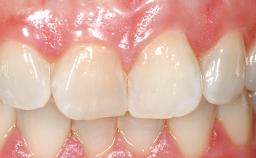

A 30-year-old female patient was referred to the office for the treatment of tooth 11. Her chief concern at the initial visit was to inquire, “Why is my tooth pink?” Upon clinical examination, it was determined that tooth 11 had a previous history of trauma and that the clinical crown had become noticeably pink in color as a result of internal resorption. This diagnosis was confirmed radiographically, indicating a large radiolucency involving the central and distal portions of the clinical crown. It was determined that restoration of this tooth was not possible, and that extraction was indicated. The presence of a mid-line diastema, which the patient wanted to reproduce, directed the treatment plan for tooth replacement utilizing a dental implant.

Prosthesis Type FDP

SAC Level Advanced

Defining Characteristics One missing tooth to be replaced by an implant-borne crown